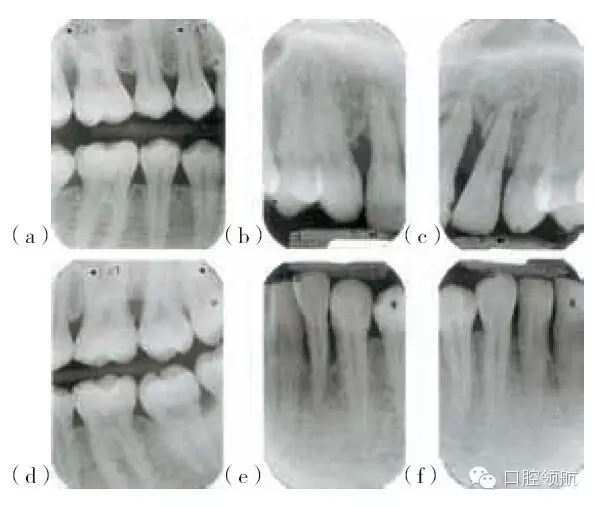

圖29.5 (a,d)圖29.4患者的X線(xiàn)片,咬合面的X線(xiàn)片顯示上頜第一磨牙遠(yuǎn)中及下頜左側(cè)

第二磨牙,有齦下牙石和牙槽骨吸收。(b,c,e,f)根尖片顯示右上側(cè)切牙,左上中切

牙及側(cè)切牙,左下側(cè)切牙有齦下牙石及牙槽骨吸收